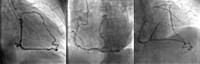

冠脉造影:见下图。

图注: 左主干(LM)开口未见,右冠状动脉(RCA)远端50%局限狭窄,前向血流TIMI 3级,RCA至冠脉左前降支(LAD)及回旋支(LCX)侧支供血至LM远端,前向血流TIMI 3级,通过侧支可见LAD近端40%弥漫狭窄,LCX远端80%~90%弥漫狭窄。